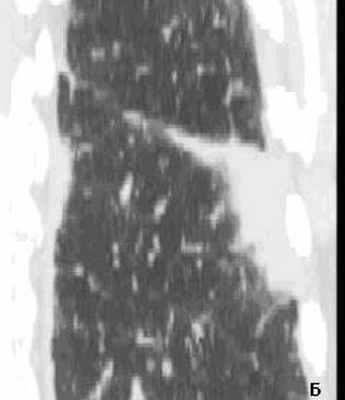

Рис. 2(А, Б). КТ грудной клетки больной Д., 80 лет. Организующая пневмония на фоне десквамативной интерстициальной пневмонии.

А - аксиальный срез на уровне нижних долей легких, выявлены участки диффузного снижения пневматизации по типу «матового стекла», в нижней доле справа выявлена субплевральная консолидация неправильной округлой формы. Б - МПР правого легкого в коронарной проекции на уровне консолидации. Рассчитанное значение 3 D – коэффициента составило 3.43 ( D max axial / D min cor = А/В =3.43), свидетельствующее в пользу доброкачественности консолидации. При трансторакальной биопсии консолидации получены клетки воспаления (макрофаги, незрелые фибробласты), внутриальвеолярные конгломераты соединительной ткани с лимфоцитарной инфильтрацией.